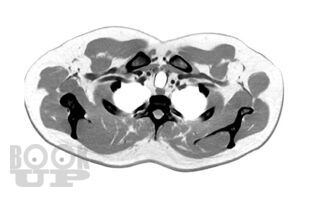

Переработанное и дополненное 3-томное издание «Sobotta. Атлас анатомии человека» является современным учебным пособием. Новое издание атласа отличается от предыдущих клинической направленностью преподавания анатомии: приведено большое количество клинических наблюдений, подтверждающих значение глубоких фундаментальных знаний анатомии при диагностике и лечении различных патологий. Это в полной мере соответствует современным требованиям, предъявляемым к медицинскому образованию, и адаптировано к новым образовательным стандартам. Атлас структурирован по региональному принципу, что соответствует темам учебных сертификационных циклов. Первый том включает разделы общей анатомии, а также подробно иллюстрирует строение костей, их соединений и мышц туловища и конечностей. Упрощенные схемы вводного характера и общие обзоры помогают понять более сложные рисунки и связи. Второй том посвящен анатомии внутренних органов грудной, брюшной полостей и органов таза. В третьем томе представлена анатомия органов головы, шеи, большой раздел посвящен нейроанатомии. Новое издание содержит высококачественные иллюстрации, дополненные подробными подрисуночными подписями. Оригинальные рисунки сопровождаются современными изображениями, полученными с помощью компьютерной и магнитно-резонансной томографии, ультразвуковых и эндоскопических методов исследования, а также интраоперационными цветными фотографиями внутренних органов и т.д. К атласу прилагаются таблицы, содержащие краткую систематизированную информацию об анатомии и о функциях мышц, суставов и об их иннервации. Использование в атласе трехъязычной терминологии повышает интерес к нему со стороны иностранных студентов, обучающихся медицине в России.